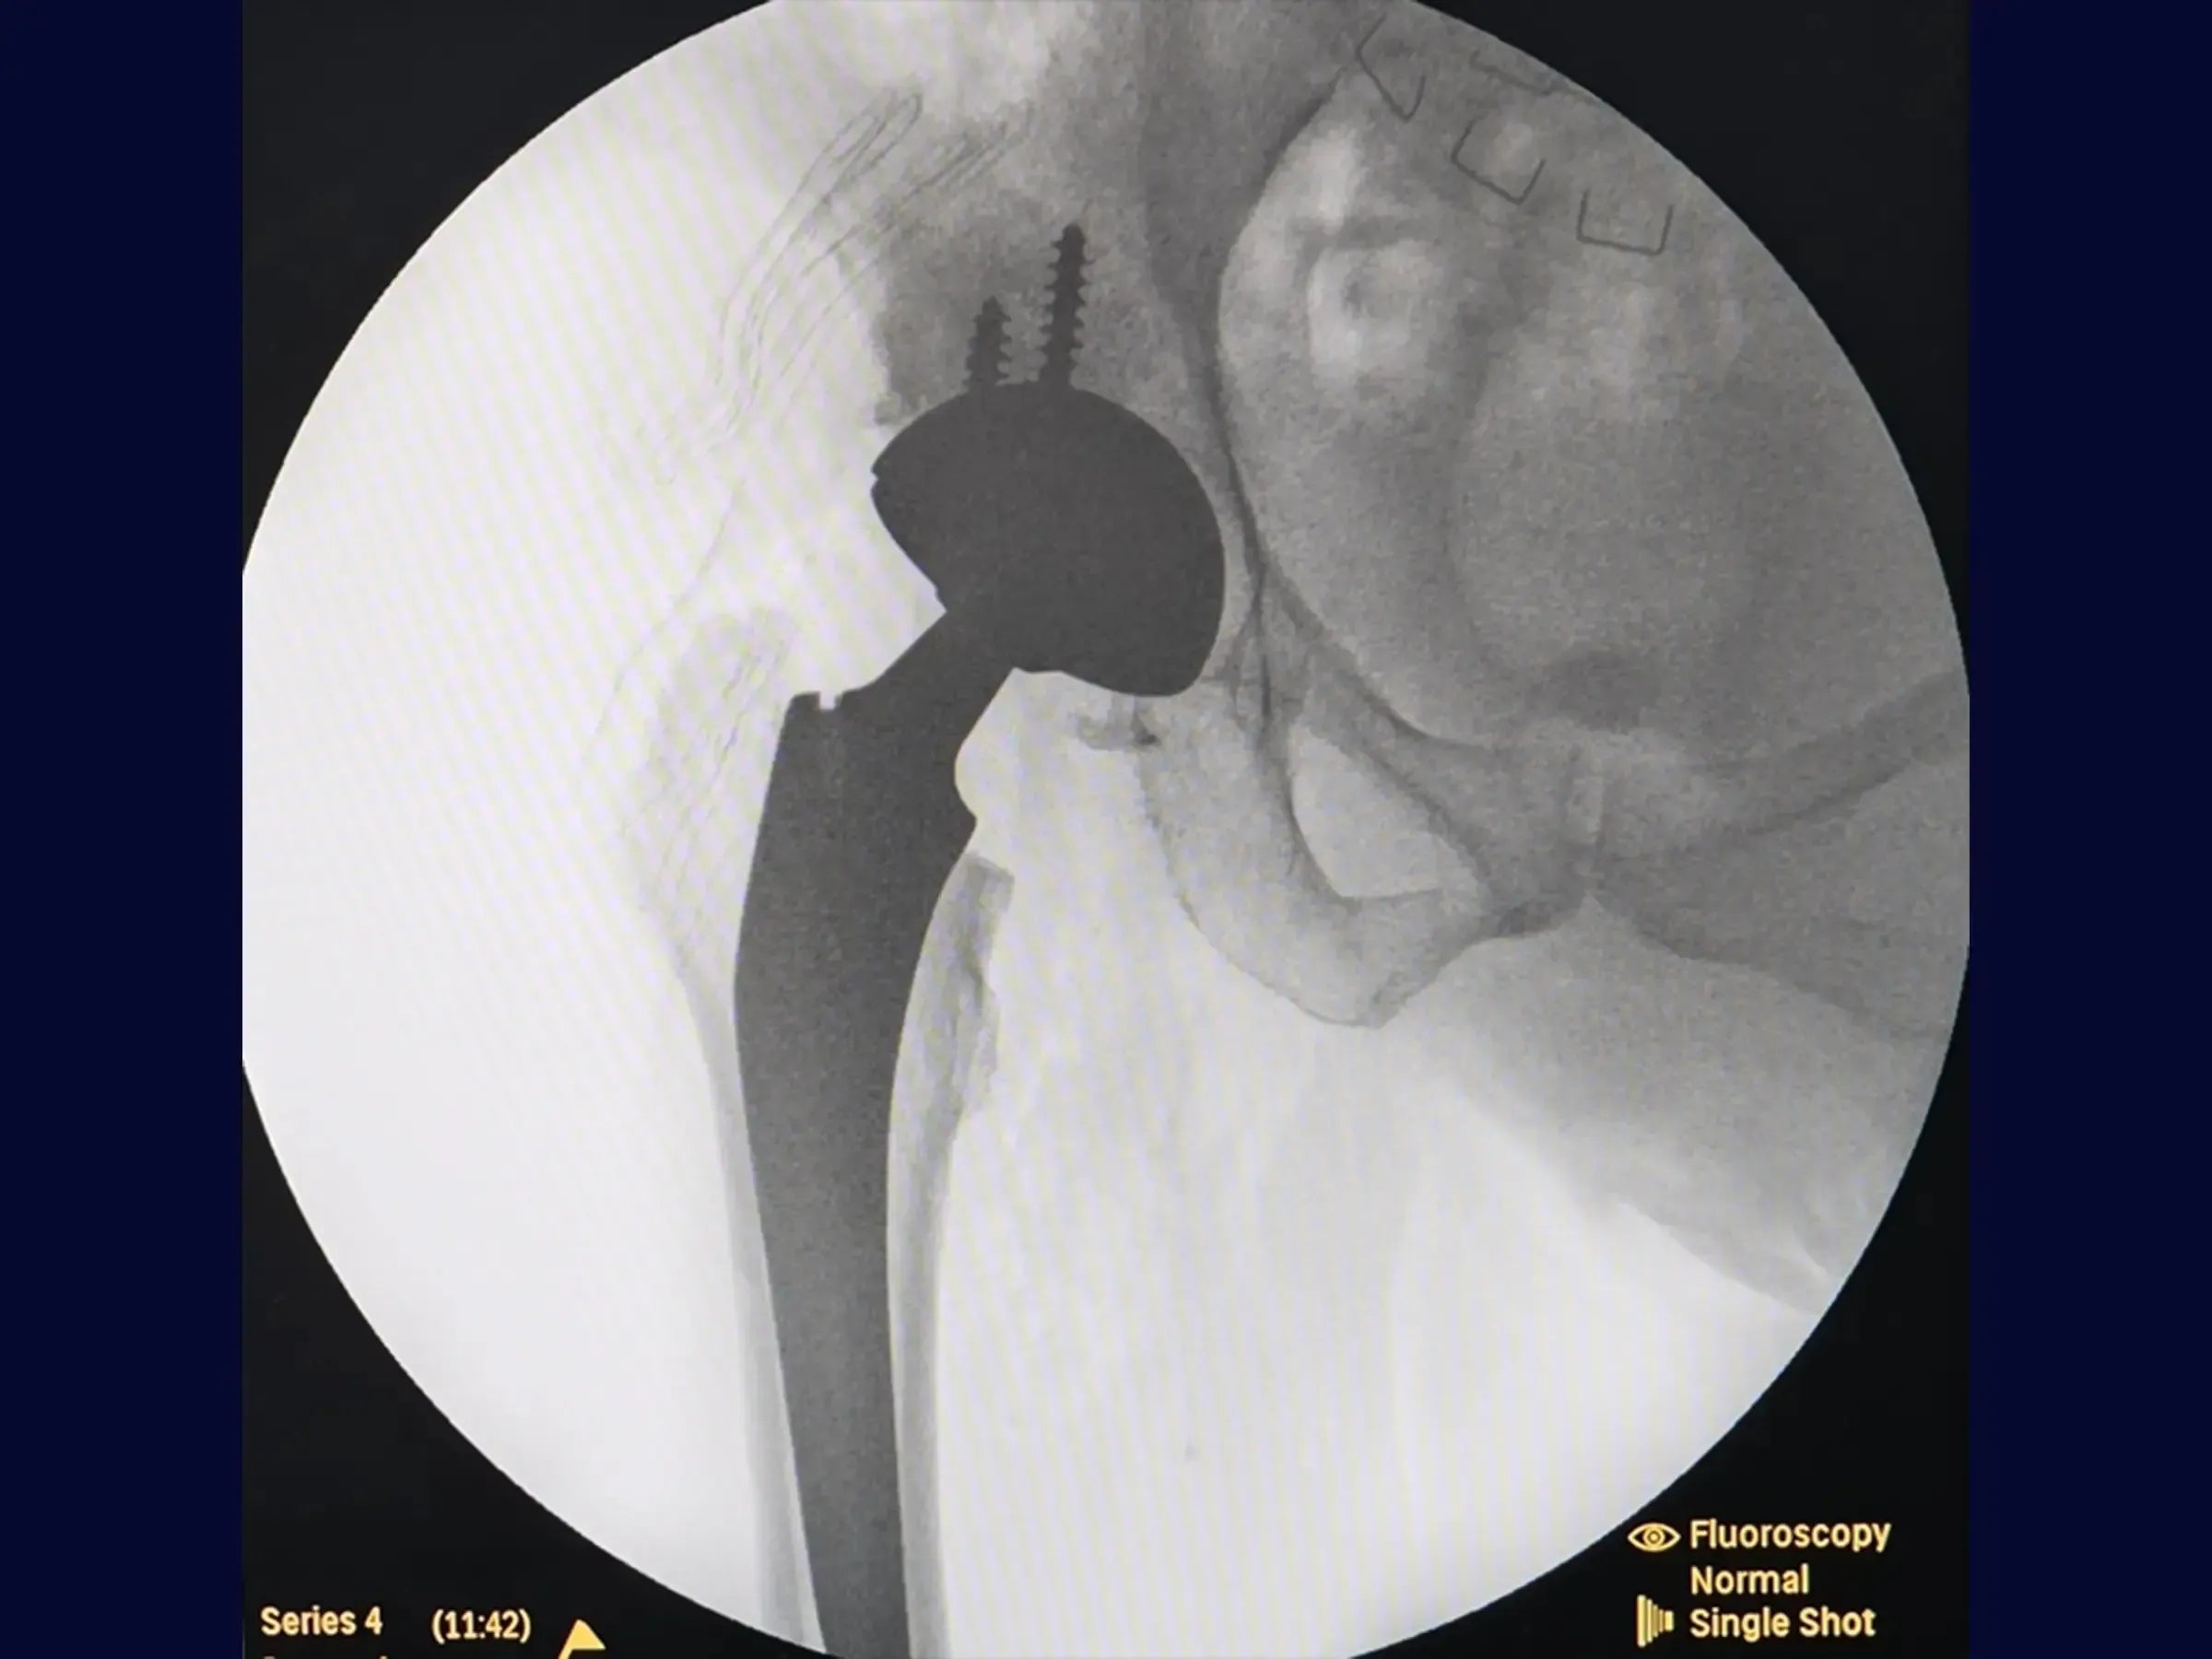

- Prueba de estabilidad y evaluación de la prótesis: Metodología para probar la estabilidad con una cabeza de prueba (iniciando con una cabeza cero) y confirmación del tamaño apropiado de los componentes.

- Inserción Definitiva y Cierre Anatómico: Abordaje sistemático de la inserción del componente definitivo, reducción de la articulación con visualización directa y cierre anatómico de los rotadores externos (incluido el piriforme).